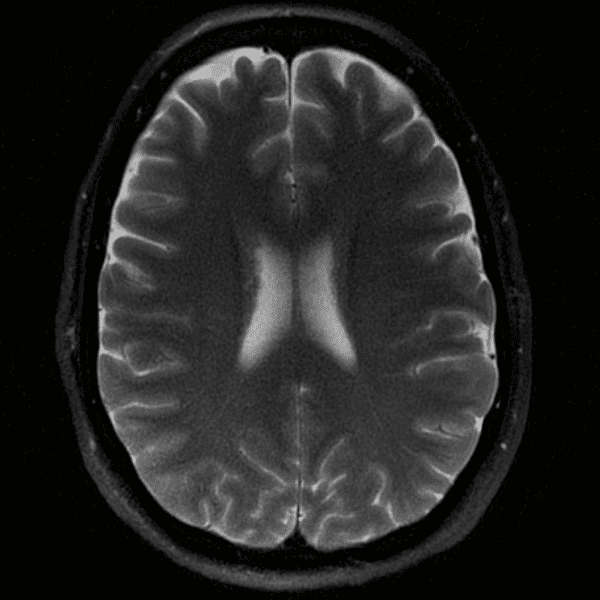

Classic Cases